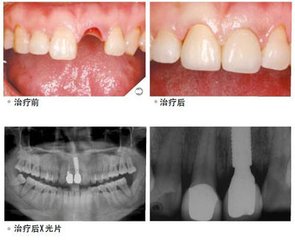

种植牙齿指的是一种以植入骨组织内的下部结构为基础来支持、固位上部牙修复体的缺牙修复方式,是目前理想的牙齿修复方法。种植牙能够获得与天然牙功能、结构以及美观效果十分相似的修复效果,宛若真牙,已经成为越来越多缺牙者的修复方式。